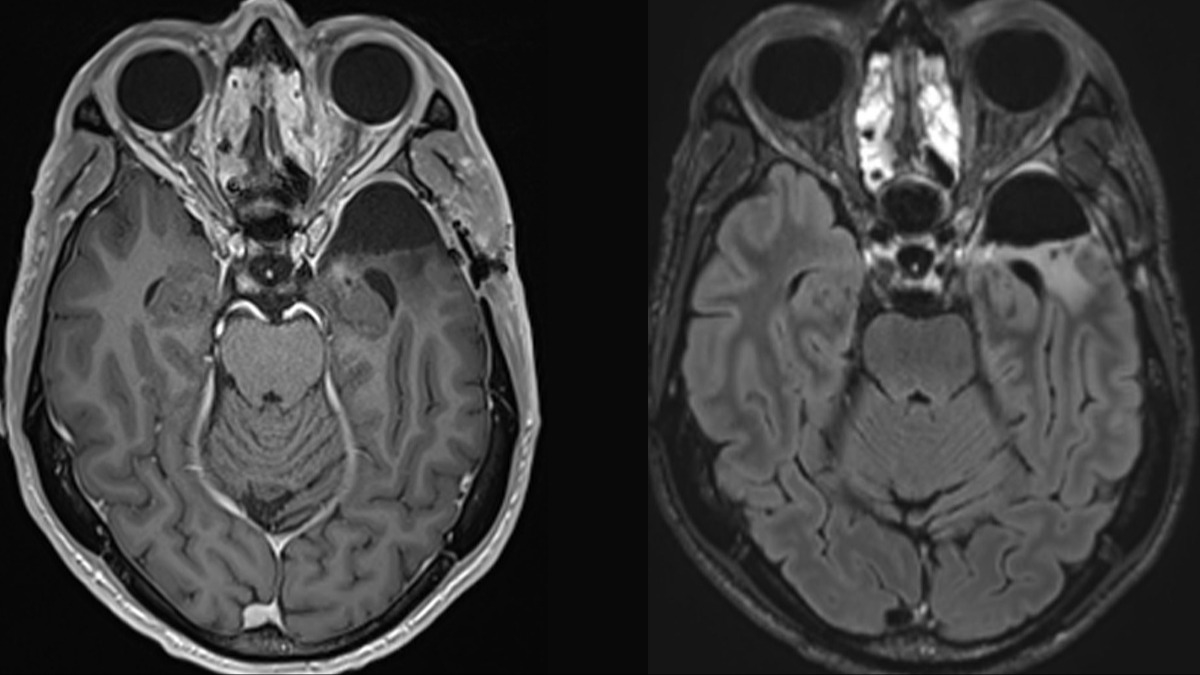

Uzman ekip eşliğinde melanomda işe yarayan ancak beyin kanserinde hiçbir zaman test edilmemiş olan yöntemlere dayanarak Dr Richard Scolyer'ın tedavisi başlandı. Ameliyatla tümörü alınan Scolyer, daha sonra kanserin tekrarlamadığını MRI taramasıyla çeşitli zamanlarda kontrol etti ve dün, son taramada kanserin tekrarlamadığını duyurdu. Dr Scolyer haberi "Geçen perşembe günü glioblastoma tekrarlaması için beyin MR taraması yaptırdım. Dün hala tekrarlama belirtisi olmadığını öğrendim. Daha mutlu olamazdım !!!!!" mesajıyla duyurdu.